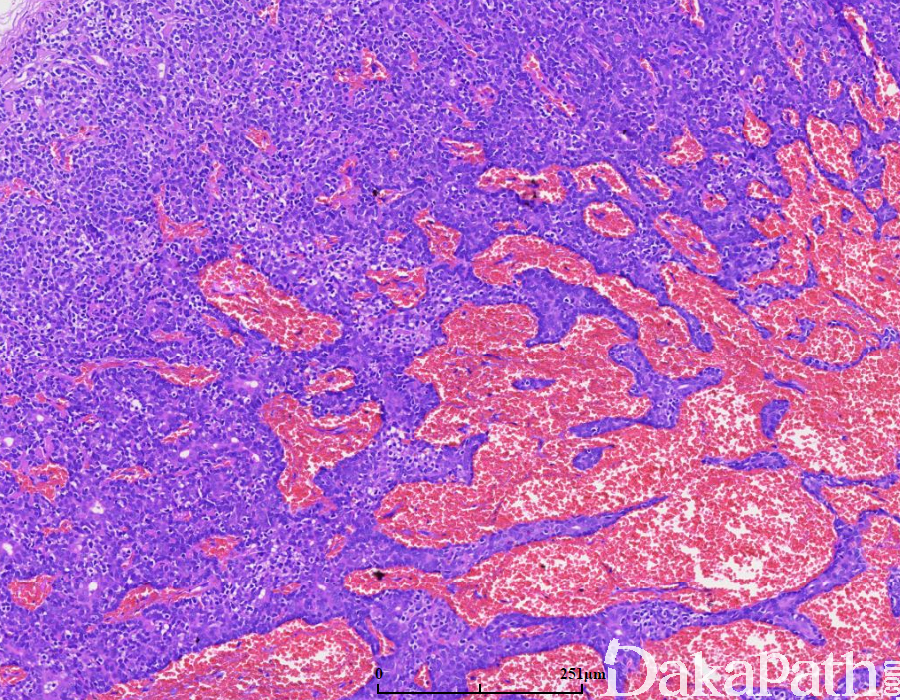

瘤体位于真皮深层,由多个或单个小叶组成,与表皮不相连,可有不完整的包膜;

小叶周边细胞体积小,基底细胞样,胞浆少,核圆形,深染;小叶中央细胞体积大,核淡染,苍白,胞浆嗜酸性;

细胞巢内有时可见局灶或弥漫小汗腺导管结构,腔内含嗜酸性 PAS 阳性耐淀粉酶物质;

间质可见玻璃样变物,有时可见淋巴细胞浸润;

部分病例间质富于血管。